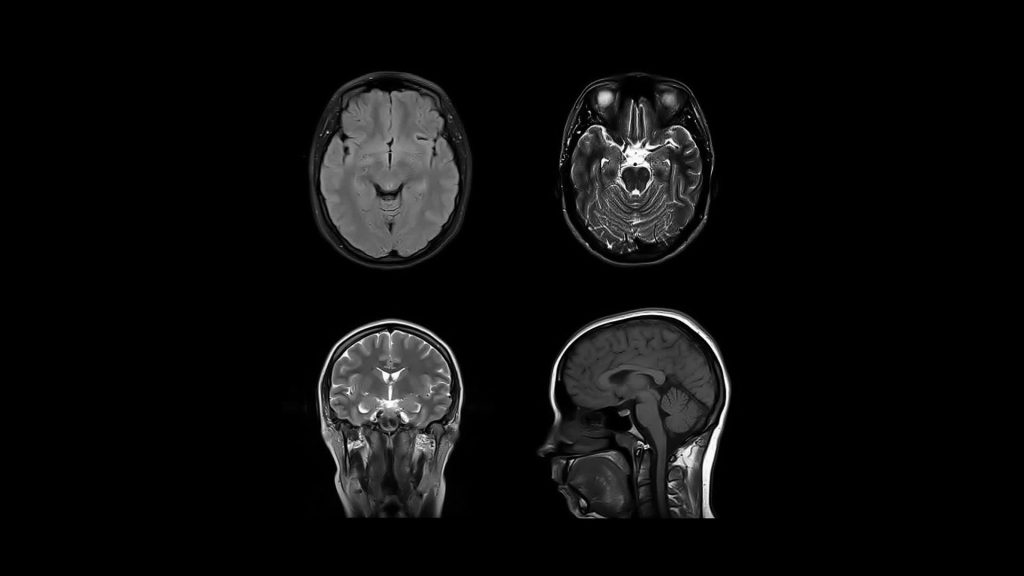

- High-Resolution Imaging

- Revolutionary Low-Field Technology Operates at just 87 mT, delivering diagnostically valuable images through advanced spatial coding algorithms.

Brain Images

Ideal for neurodegenerative and cardiovascular disease follow-up. Enables routine imaging without radiation exposure. Suitable for outpatient clinics, ambulatory centers and primary care. Early-preliminary diagnosis, chronic care tracking.